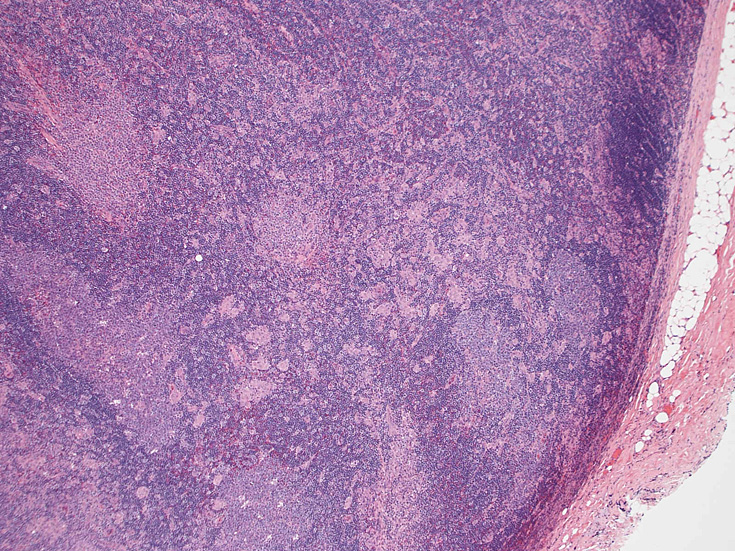

通常傍濾胞領域に小型, 不整形の類上皮細胞肉芽腫が多数形成されている。この症例では慢性炎症を伴い線維性に肥厚した皮膜直下にも多くの肉芽腫病変が散在する。Piringer型リンパ節炎と呼ばれる。

皮質から傍皮質に肉芽腫が散在大小不整な肉芽腫looseな肉芽腫皮膜下にも肉芽腫あり